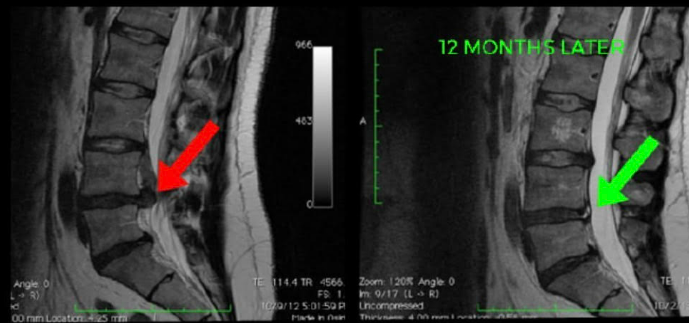

Successful physio for a pinched nerve in the lower back involves 3 aspects: Symptom reduction, Activity modification & lower back, pelvic and hip strengthening